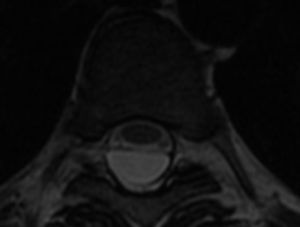

Mediante RM craneal con y sin contraste y angio-RM venosa se descartaron lesiones ocupantes de espacio, alteraciones de la charnela occipitocervical, trombosis de senos venosos y captaciones patológicas de contraste. Se realizó punción lumbar, que muestra LCR de aspecto claro con presión de apertura de 15cm de agua, acelular, glucorraquia normal y proteínas elevadas (81mg/dl). Se completó el estudio con RM medular, objetivándose colecciones líquidas sugestivas de quistes aracnoideos, intradural desde el nivel T1-T2 hasta T9 (fig. 1) y extradural (fig. 2) desde T11 hasta L5, que ocasionan desplazamiento anterior de la médula y de las raíces de la cola de caballo; no se objetivó realce tras la administración de contraste. El paciente desestimó tratamiento quirúrgico.